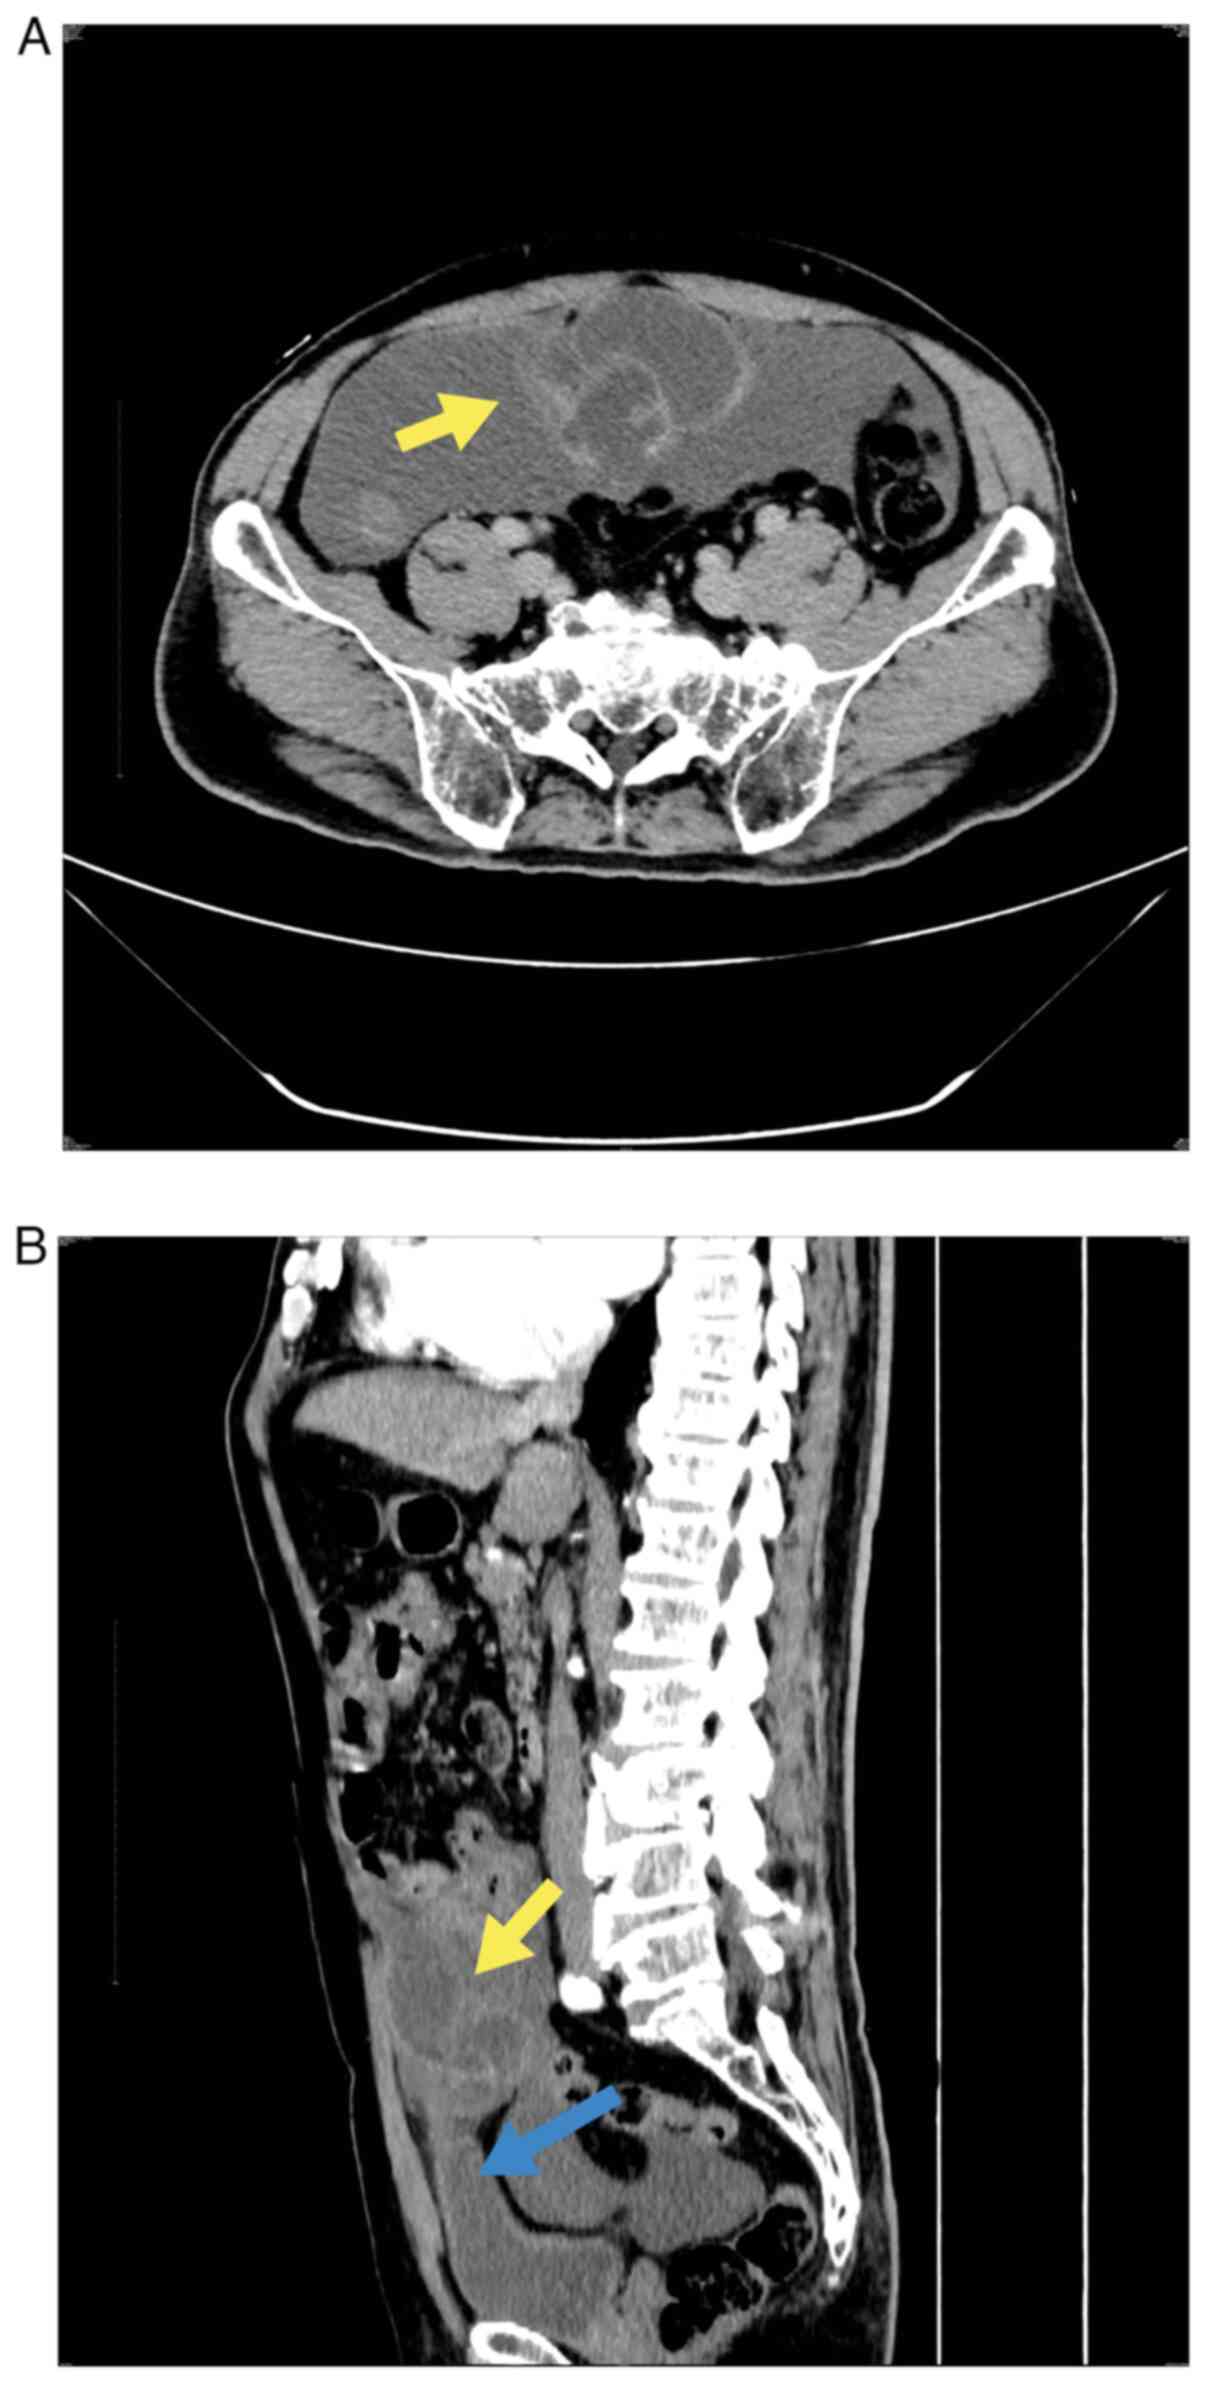

A 74-year-old male patient visited the Department of Emergency Surgery of Xiaoshan Affiliated Hospital of Wenzhou Medical University (Hangzhou, China) on 24th June 2022, because of right lower abdominal pain. The patient had persistent distension pain in the right lower abdomen 1 day prior to paroxysmal aggravation. An abdominal computed tomography (CT) scan indicated multilocular cystic lesions around the urachal duct (Fig. 1A) at the anterior upper margin of the bladder (Fig. 1B). The wall of the capsule was significantly enhanced, accompanied by ascites and extensive exudation in the abdomen and pelvic cavity. Malignant urachus tumors with peripheral dissemination were also considered. A physical examination of the abdomen and routine blood (white blood cell series, red blood cell series and platelet series) and biochemical tests (blood glucose, lipids and transaminases) all revealed no abnormalities. Hematologic tumor markers demonstrated that carbohydrate antigen 19-9 (CA19-9) was normal, while carcinoembryonic antigen (CEA) was increased at 13.95 µg/l (reference value, 0-5 µg/l) and carbohydrate antigen 125 (CA125) was increased at 41.3 kU/l (reference value, <35.0 kU/l). The medical history of the patient revealed that the patient had undergone lithotripsy for left ureteral calculi in 2017 and 2019. A preoperative CT scan of the urinary system revealed pelvic cystic lesions in both cases. A urachal cyst with calculi was considered but was not treated, because the patient had no discomfort. In addition, the patient had hypertension and diabetes for >10 years, but the blood pressure and sugar levels of the patient were well controlled. Exploratory laparotomy was performed by a urological surgeon on 5th July 2022. During surgery, a mass with a diameter of ~10 cm was revealed in the urachus, which adhered to the peritoneum below the umbilical tract and was connected to the top of the bladder below the mass. There were two small lacerations ~1 cm long, and a large amount of yellow jelly-like mucus was observed leaking out of the mass; the majority of the intestine was coated in the mucus. Rapid pathological examination of the excised mass during the operation suggested a mucinous tumor. Mucinous adenocarcinoma could not be excluded because of the formation of a large number of mucous lakes and the presence of cell atypia (although only mild). Therefore, radical resection of the urachal tumor and release of the intestinal adhesions were performed. During the operation, the mass, adhesion peritoneum and part of the bladder wall, ~1 cm from the mass, were completely removed. The appendix was normal in size and shape. After the bladder was rinsed with normal saline, the incision was sutured, and the abdominal cavity and intestines were rinsed with a large amount of sterilized water by injection to remove the jelly-like mucus.

Figure 1

Abdominal contrast-enhanced computed tomography examination. (A) Multilocular cystic mass (yellow arrow) in the urachus area with a significant enhancement of the cyst wall and extensive exudation in the abdominal pelvic cavity. (B) The cystic mass (yellow arrow) is attached to the top of the bladder (blue arrow).